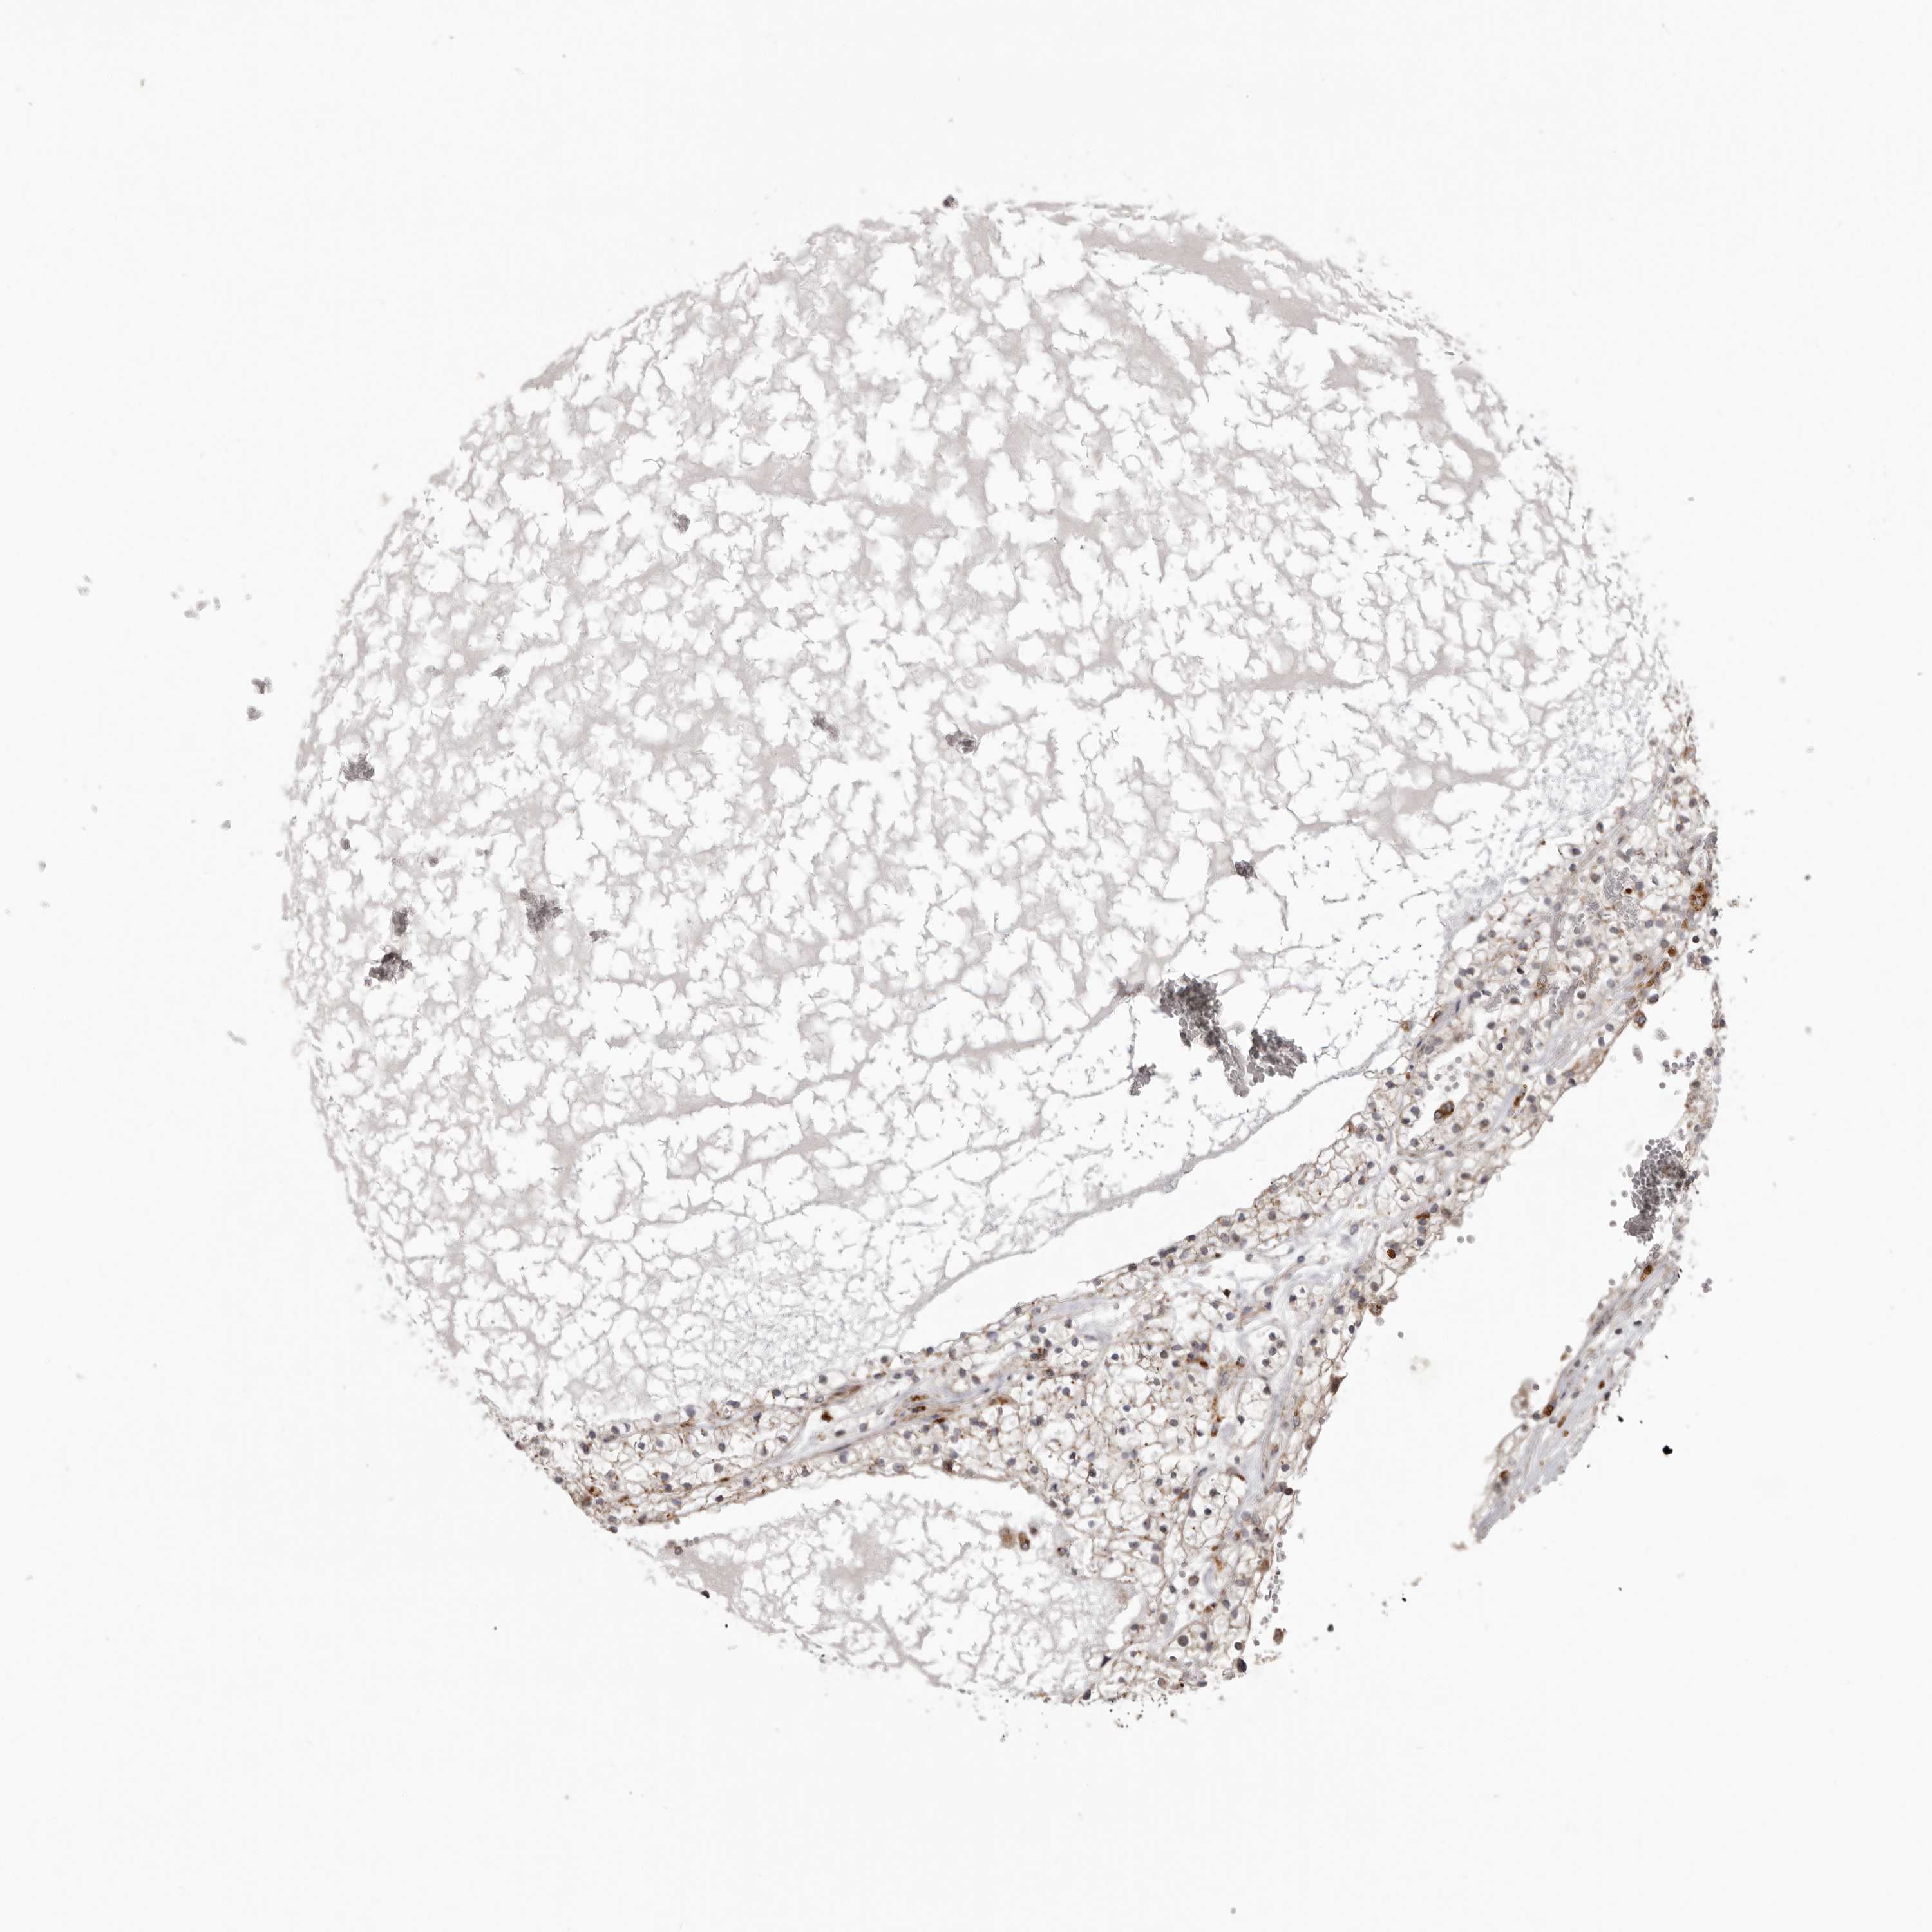

KIDNEY RENAL CLEAR CELL CARCINOMA (VALIDATION) - Interactive survival scatter ploti

The Survival Scatter plot shows the clinical status (i.e. dead or alive) for all individuals in the patient cohort, based on the same data that underlies the corresponding Kaplan-Meier plots. Patients that are alive at last time for follow-up are shown in blue and patients who have died during the study are shown in red.

The x-axis shows the expression levels (FPKM) of the investigated gene in the tumor tissue at the time of diagnosis. The y-axis shows the follow-up time after diagnosis (years). Both axes are complimented with kernel density curves demonstrating the data density over the axes. The top density plot shows the expression levels (FPKM) distribution among dead (red) and alive patients (blue). The right density plot shows the data density of the survived years of dead patients with high and low expression levels respectively, stratified using the cutoff indicated by the vertical dashed line through the Survival Scatter plot. This cutoff is automatically defined based on the FPKM cutoff that minimizes the p-score. The cutoff can be changed by dragging the vertical line or by entering a cutoff value in the square labeled "Current cut-off".

Under the Survival Scatter plot the p-score landscape (black curve; left axis) is shown together with dead median separation (red curve; right axis). Dead median separation is the difference in median mRNA expression between patients who have died with high and low expression, respectively. It is calculated as follows: median FPKM expression of dead patients with high expression - median FPKM expression of dead patients with low expression. This is intended to aid the user in visually exploring custom cutoffs and the associated p-scores and dead median separation.

Individual patient data is displayed and can be filtered by clicking on one or more of the category buttons on the top of the page. Categories describing expression level and patient information include: high, low, alive, dead, female, male and tumor stages. The scale of the x-axis can be toggled between linear and log-scale by clicking on the "x log" button. Mouse-over function shows TCGA ID, patient information and mRNA expression (FPKM) for each patient.

& Survival analysisi

Kaplan-Meier plots summarize results from analysis of correlation between mRNA expression level and patient survival. Patients were divided based on level of expression into one of the two groups "low" (under cut off) or "high" (over cut off). X-axis shows time for survival (years) and y-axis shows the probability of survival, where 1.0 corresponds to 100 percent.

NUP43 is not prognostic in Kidney Renal Clear Cell Carcinoma (validation)

Best expression cut offi

Based on the FPKM value of each gene, patients were classified into two groups and association between prognosis (survival) and gene expression (FPKM) was examined. The best expression cut-off refers the FPKM value that yields maximal difference with regard to survival between the two groups at the lowest log-rank P-value. Best expression cut-off was selected based on survival analysis .

When clicking on this number, the vertical dashed line indicating cut-off, the interactive survival plot, and the Kaplan-Meier curve will be adjusted to show results based on the best expression cut-off.

: 11.53

TCGA RNA samplesi

RNA-seq data is reported as average FPKM (number Fragments Per Kilobase of exon per Million reads), generated by the The Cancer Genome Atlas (TCGA) .

Normal distribution across the dataset is visualized with box plots, shown as median and 25th and 75th percentiles. Points are displayed as outliers if they are above or below 1.5 times the interquartile range. FPKM values of the individual samples are presented next to the box plot.

Average pTPM 12.9

Number of samples 100